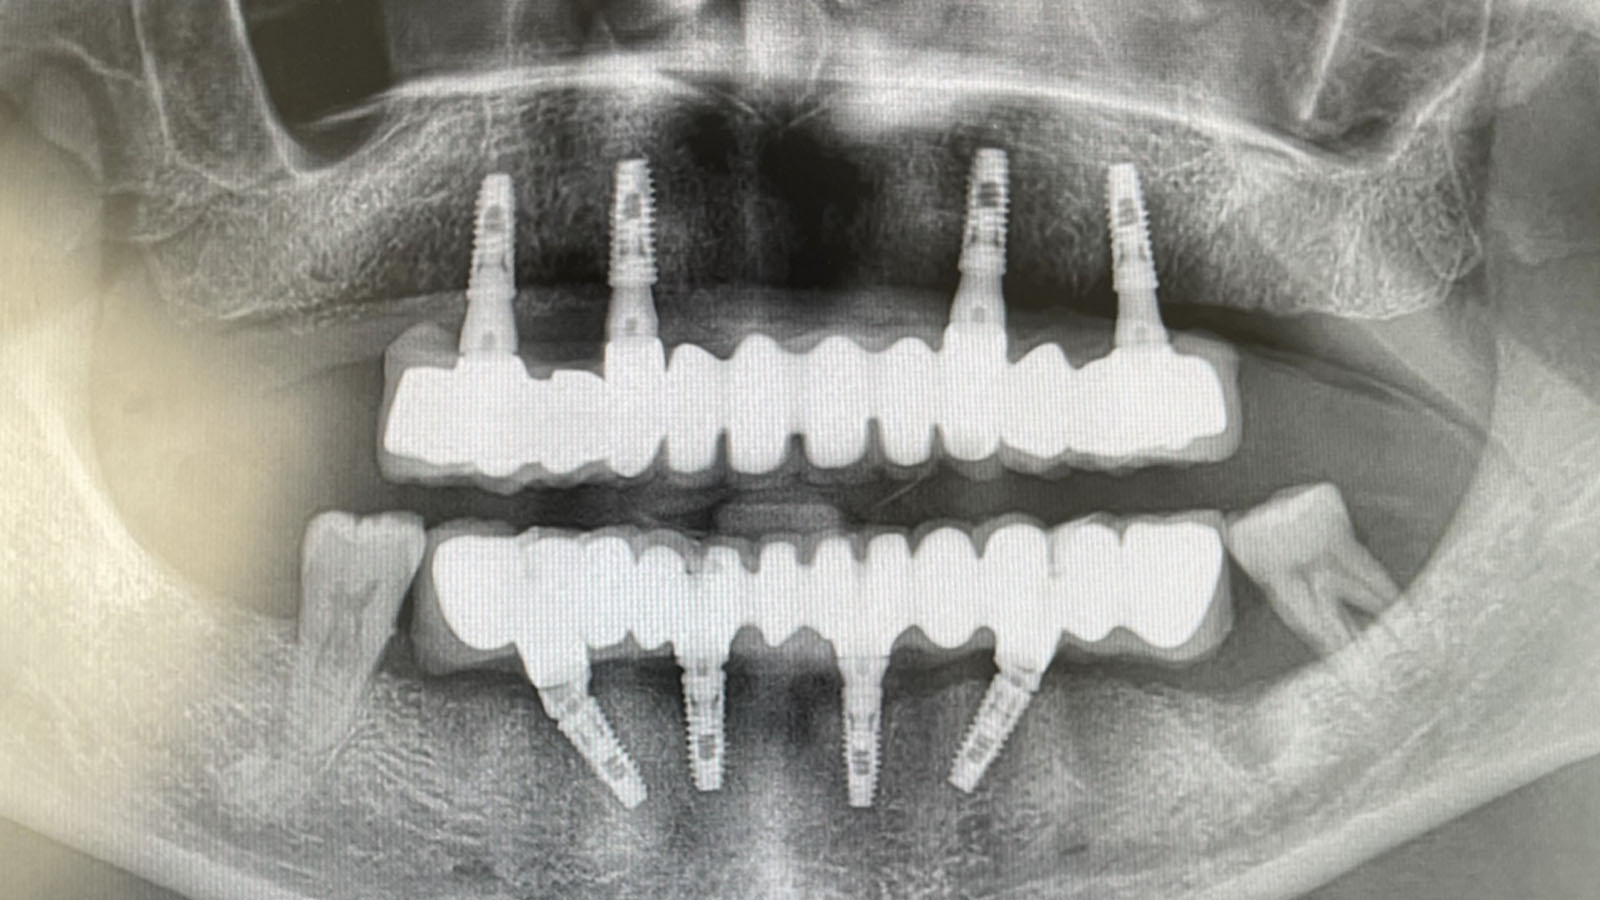

First of all a detailed clinic and radiological examination should be done to patients for who All On Four treatment is planned. By making meausrements through computerized tomography (BT) a suitable plan is made for the patient.

All On Four procedure is composed of two parts as surgery and dental prothesis process. After 4 pieces of dental implants are applied to the patient on the first day of treatment, temporary dental prothesis is fixed on dental implants on the same day. 3 months later permanent teeth prothesis is applied to patient